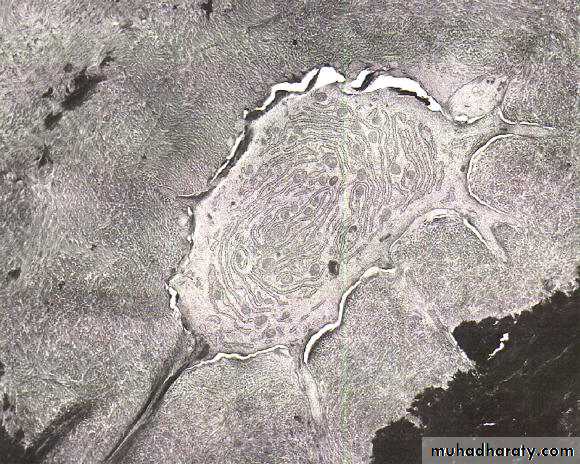

As a result of continuous phasic deposition of cementum, resting lines known Salter lines appear in cementum .

Incremental lines of Salter

Incremental LinesIncremental lines of Salter.